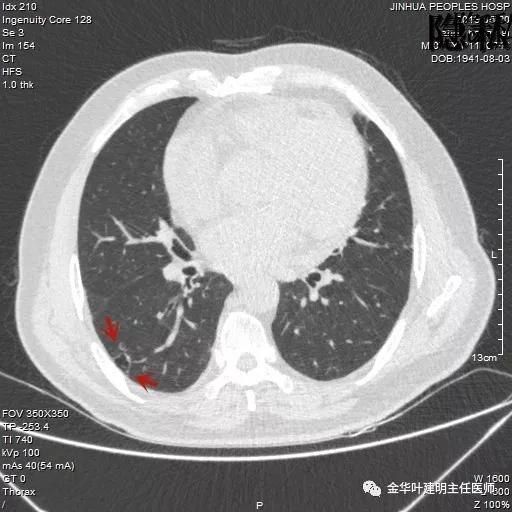

考虑恶性,那么就得考虑住院并行手术治疗,入院后再进一步查靶扫描,结果如下:

是不是囊腔型腺癌?周围病灶,有空腔,有磨玻璃成份,当然要考虑,但我觉得因为似乎是以往是空腔性病变,今年其内部分填充了实性成分,要考虑粘液腺癌可能为大。当然反正都得手术切除治疗。

经过必要的术前准备,我们予以行“单孔胸腔镜下右肺下叶部分切除术”,当然按理也可先楔形切除后,送快速切片,如果报浸润性腺癌,那么可再行下叶切除并淋巴结清扫,也可以行右肺下叶背段切除术。但我考虑一来患者已经78岁高龄,二来病灶进展也不算快,相对局限,为了生活质量不受明显影响,还是拟仅行右下叶部分切除。结果术后病理居然是鳞癌!当然具体类型腺癌还是鳞癌,抑或微浸润腺癌都是次要的,主要的是我们要判断出病灶是良性还是恶性,是否需要手术切除?手术方式个体化,如何达到效果相当而对机体影响更小。

这样的鳞癌不常见!!